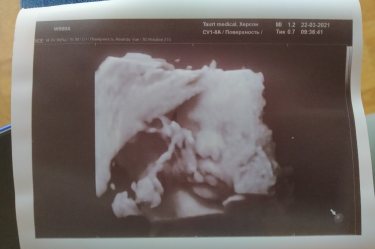

Вчера были на УЗИ 😍

Наше 1фото ?